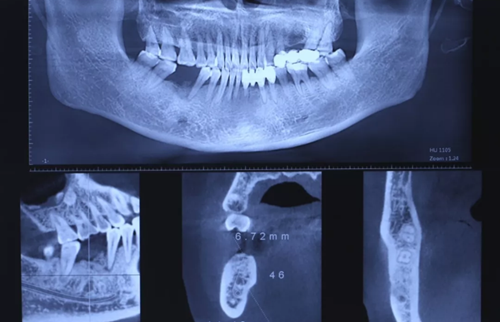

3、術(shù)前全景片

46牙烤瓷冠修復(fù),根折伴大范圍骨吸收。(攝于2016年8月31日)

10、CBCT檢查

CBCT檢查測(cè)量缺牙區(qū)可用骨高度14.40mm,骨寬度6.72mm。

(攝于2017年2月15日)